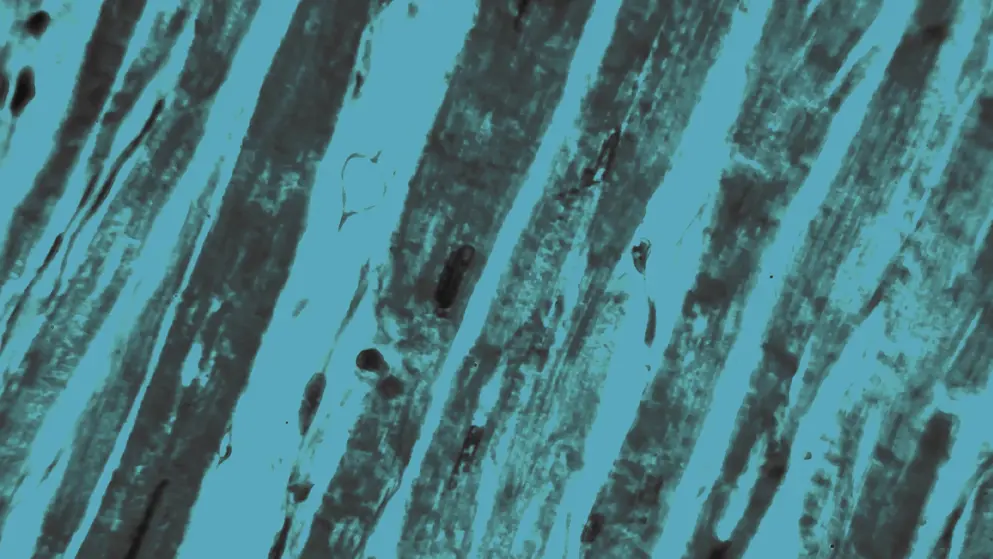

Heart failure (HF) is a cardiac condition caused by structural or functional impairment of ventricular filling or ejection of blood. It is classified based on left ventricular ejection fraction (LVEF) into four categories: HF with reduced EF (LVEF ≤40%), HF with mildly reduced EF (LVEF 41–49% with clinical evidence of HF), HF with preserved EF (LVEF ≥50%), and HF with improved EF (LVEF >40% in patients with previously documented LVEF ≤40%).

HF is often associated with various underlying conditions that can either directly damage the myocardium or increase cardiac workload. Ischemic heart disease is the most common cause of HF; however, other conditions like myocardial infarction, hypertension, cardiomyopathy, myocarditis, arrhythmias, diabetes, and obesity are also risk factors.